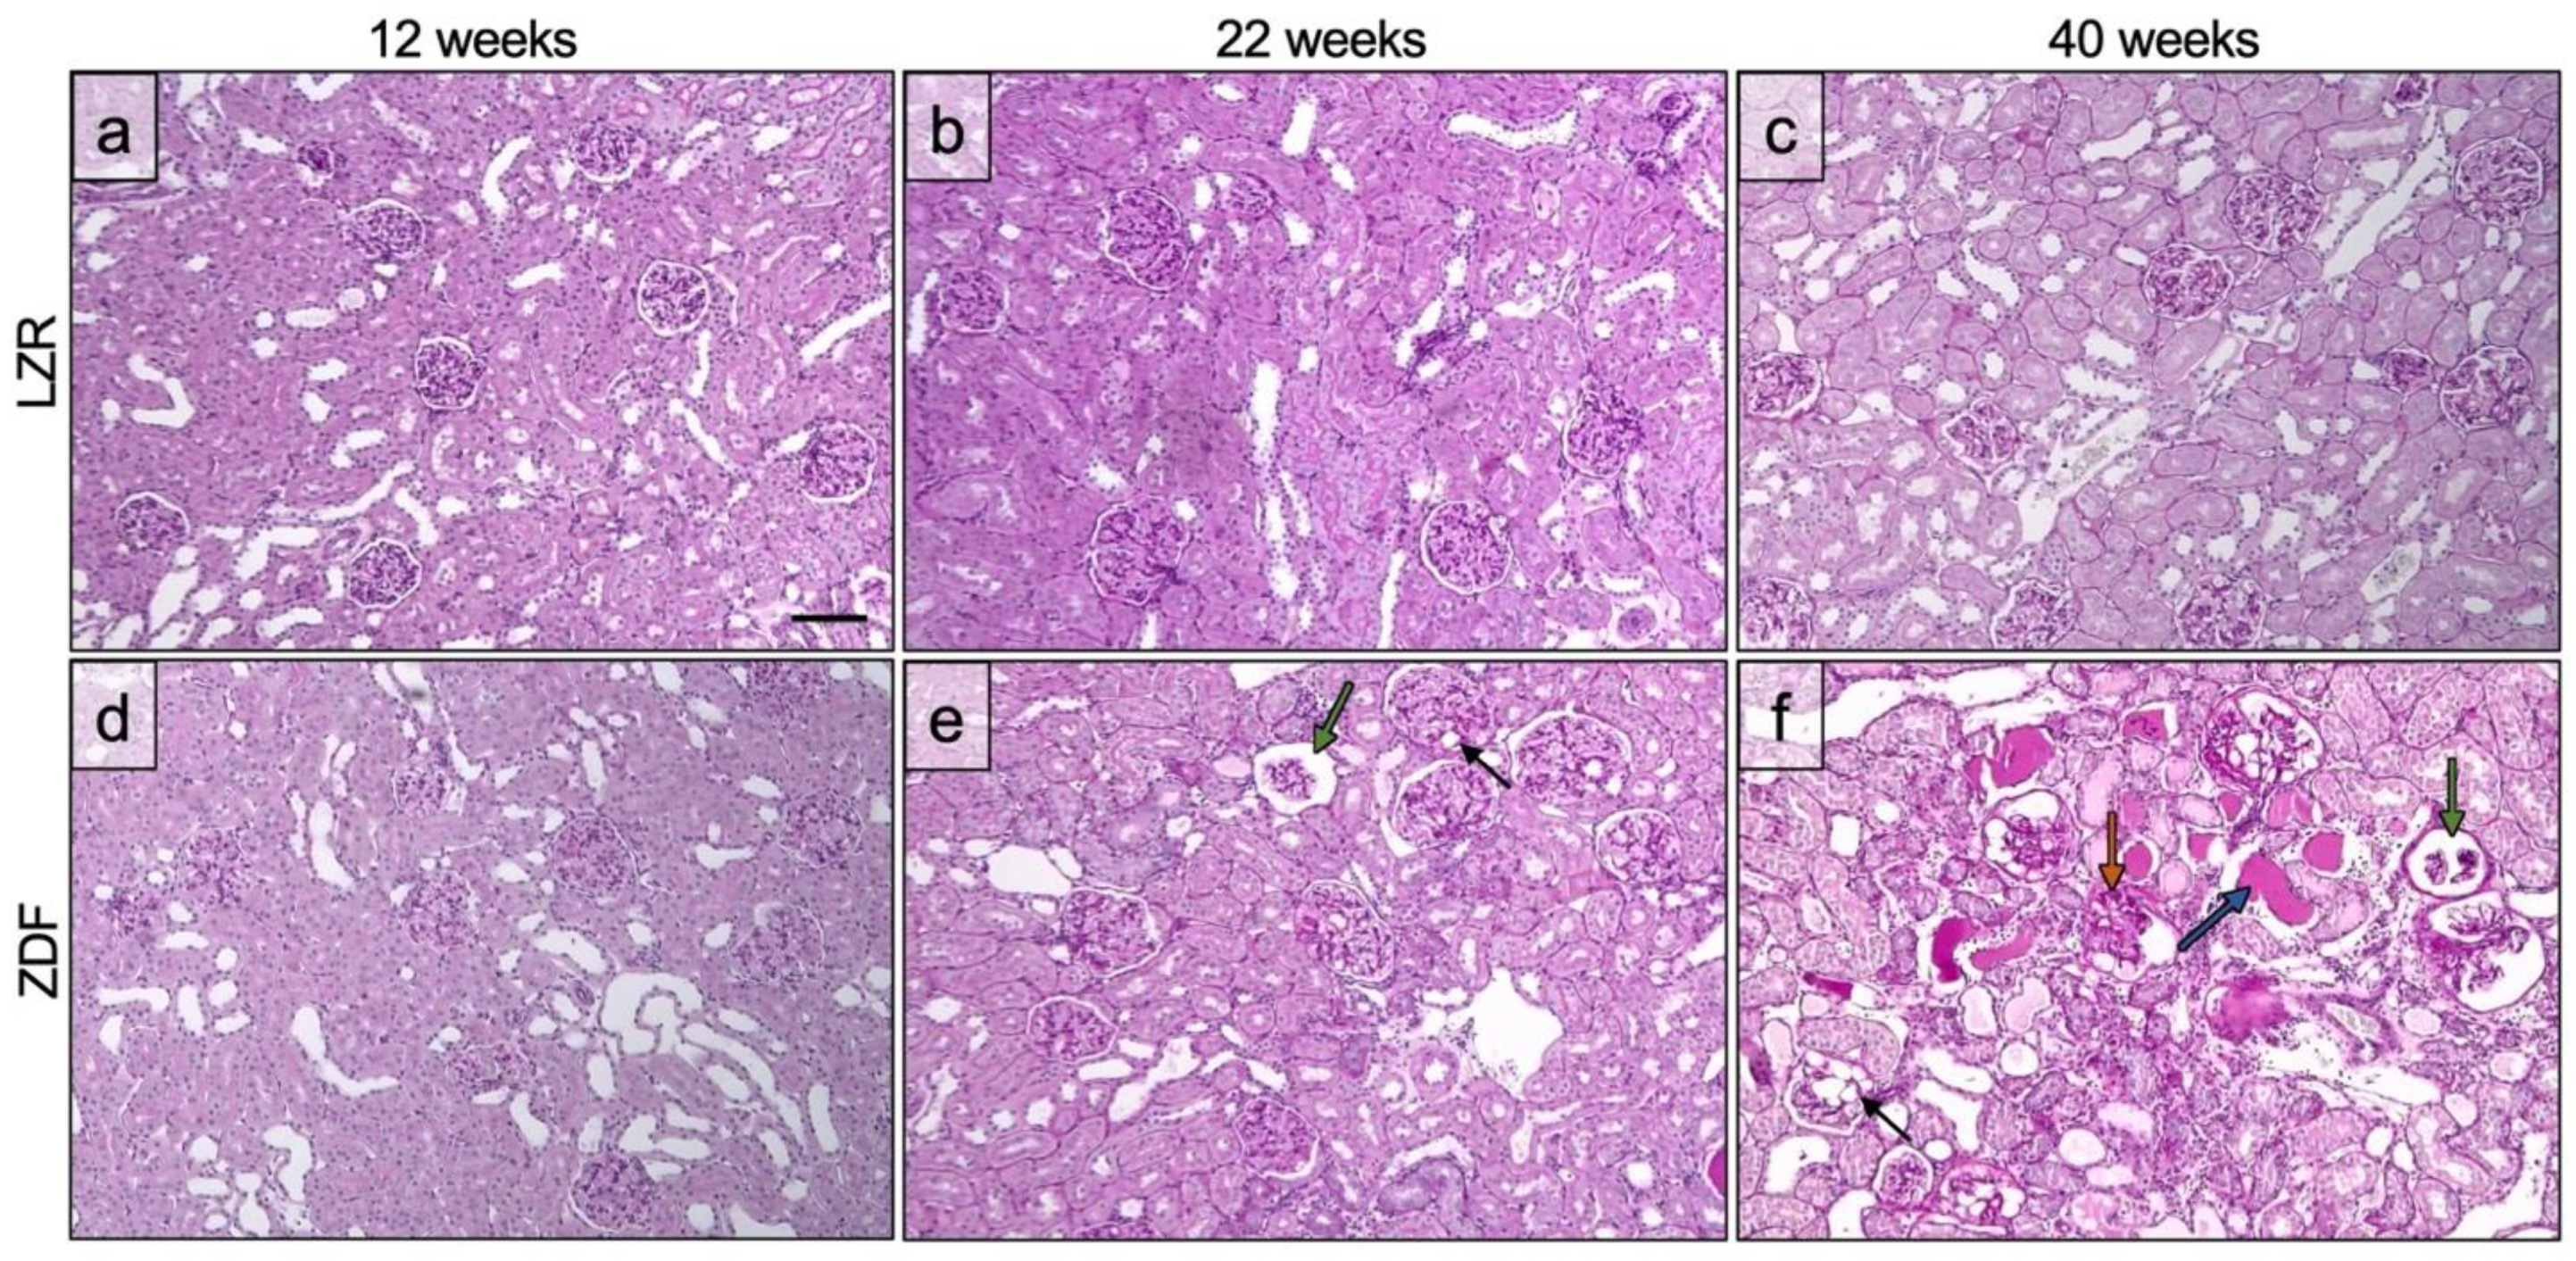

3.2. Glomerulopathy Grading

3.3. Quantified Measurements from SRUS